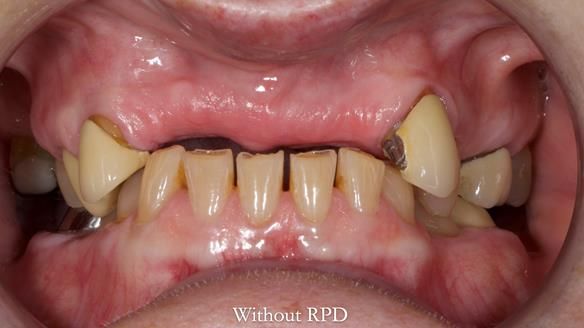

This is one of those cases that reminds me why I love removable prosthodontics. Pam was an absolute joy to treat — we were on the same page throughout. Her old upper flexible denture was loose, uncomfortable, and unaesthetic. We replaced it with a carefully designed metal-based upper partial denture/splint and new porcelain-bonded-to-zirconia (PBZ) crowns for the canines. The result is stable, comfortable, and natural-looking.

- Diagnosis and plan – Flexible upper denture ill-fitting with poor stability, retention, and appearance. Plan: metal-based upper partial denture/splint with lighter porcelain-bonded-to-zirconia crowns on UR3 and UL3.